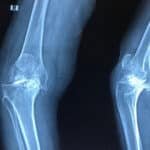

Joint replacement surgery is a surgical method of replacing the joint with an artificial or prosthetic joint, because the original joint is damaged or worn out. The treatment is very effective in patients with advanced arthritis, a fracture, or damage to a joint that cannot be managed with non-operative measures. We are recognized as the best joint replacement surgery orthopedic hospital in Madurai, able to complete your knee and hip replacement, regardless of your situation, using the best joint replacement techniques and facilities.

- Total Knee Replacement Surgery in Madurai- In which the entire joint is replaced in a patient with advanced arthritis.

- Partial Knee Replacement Surgery in Madurai- Where only the damaged part of the knee joint is replaced and is accomplished quicker than knee replacement surgery.

Total Knee Replacement Surgery in Madurai

- Total Knee Replacement Surgery in Madurai – Involves replacing the entire joint for patients experiencing severe arthritis.

- Partial Knee Replacement Surgery in Madurai – Also known as “Unicompartmental knee replacement,” it involves replacing only the diseased compartment of the knee, resulting in a faster recovery time.